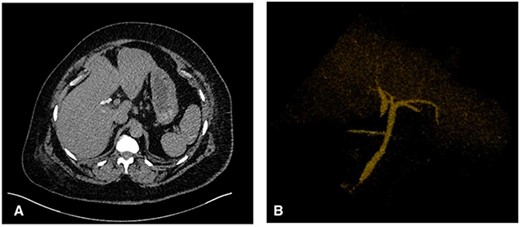

Abdominal ultrasound revealed a thickened gallbladder wall measuring 3.6 mm, mobile sludge, small amounts of pericholecystic fluid and a positive sonographic murphy’s sign (Fig. 1). As such, the diagnosis of acute cholecystitis was made, and the patient underwent a LC.

(A) Transverse view of the gallbladder showing a 3.6 mm wall diameter. Inferior arrow also shows small stones and sludge. (B) Longitudinal view of the gallbladder again showing mobile sludge. (C) Longitudinal view of the gallbladder showing a small amount of pericholecystic fluid. (D) Measurement of the CBD diameter at 5.4 mm (within normal limits).